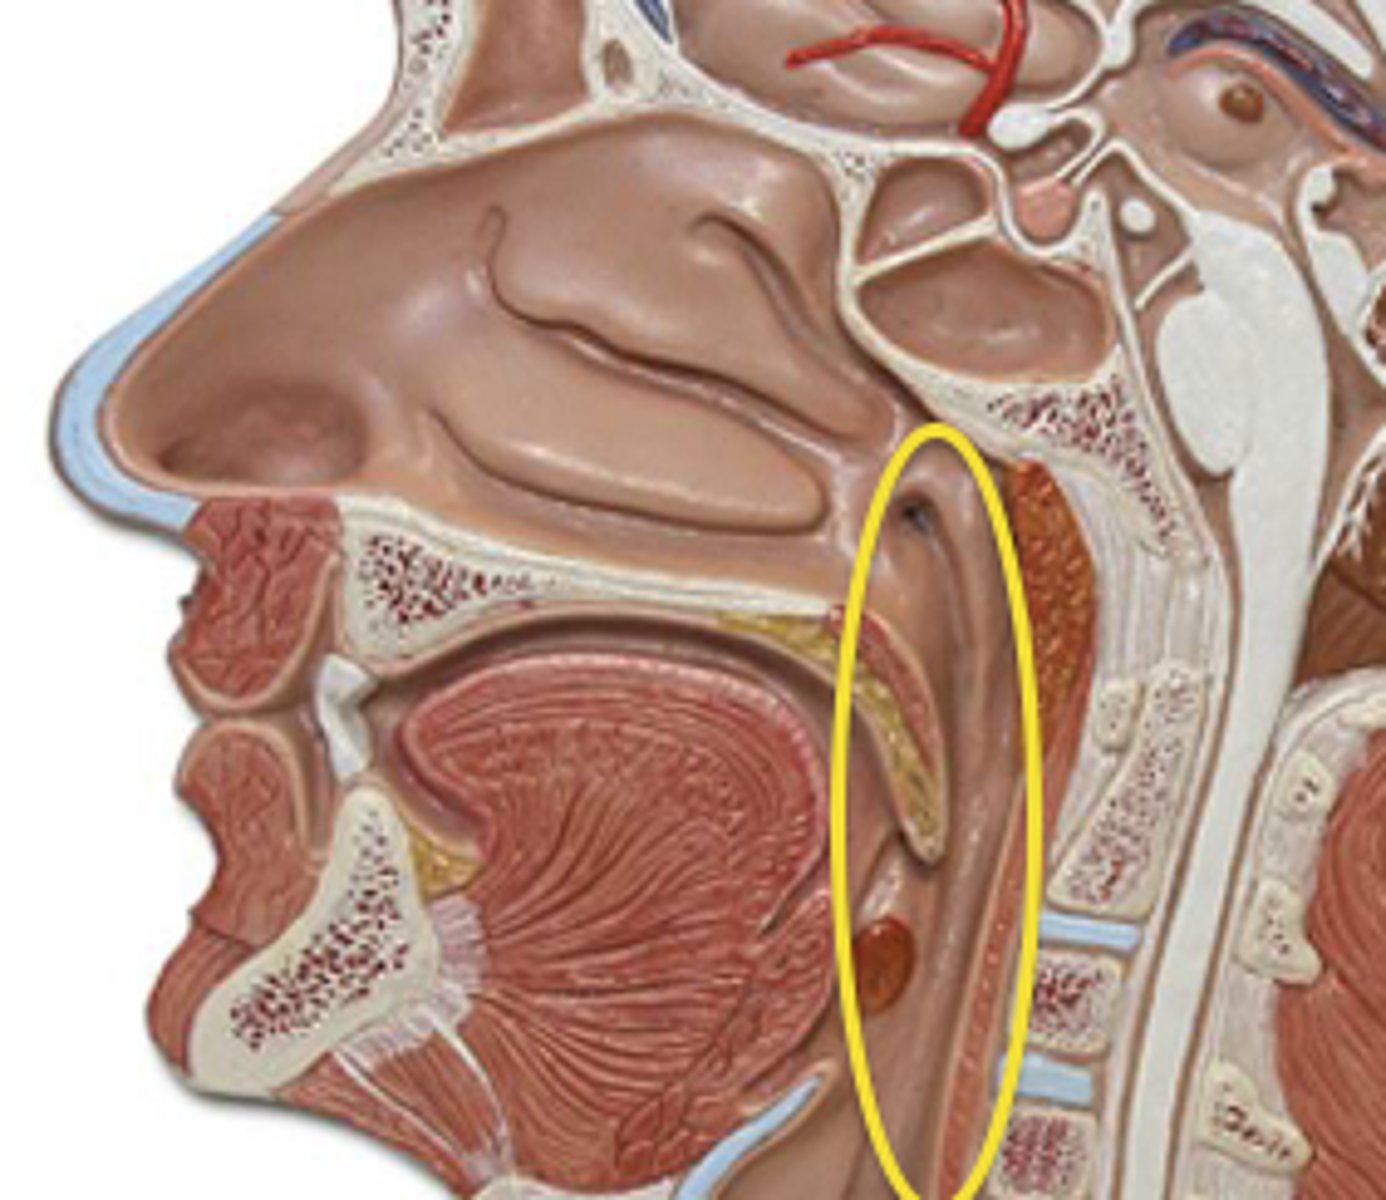

Superior Constrictor Figure

Superior Constrictor Description

Weakest, but most complex of the three

Forms nasopharyngeal and upper

oropharyngeal walls

Origin - sphenoid, mandible, pterygomandibular ligament

Course - posterior, then medial

Insertion - midline raphe

Action - may contribute to velopharyngeal closure by moving posterior wall of pharynx

anteriorly